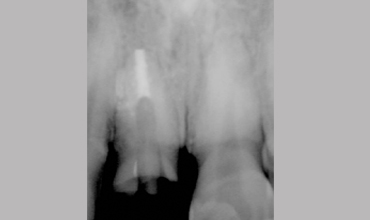

Management Of Fractured Central Incisor With Biological Post